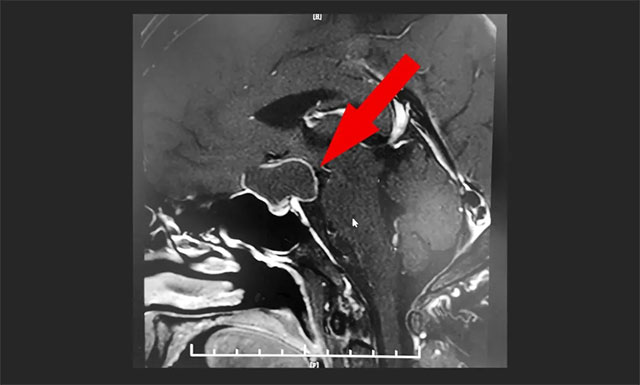

鞍區(qū)MRI平掃+增強顯示,鞍上區(qū)大囊樣占位,增強掃描薄壁強化,灶矢橫高徑約3*2*2cm;鞍上結(jié)構(gòu)(下丘腦、視交叉)均受壓,鞍隔下塌,鞍底腺垂體稍變扁,其左側(cè)份強化欠均勻。

▲ MR顯示鞍上區(qū)大囊樣占位